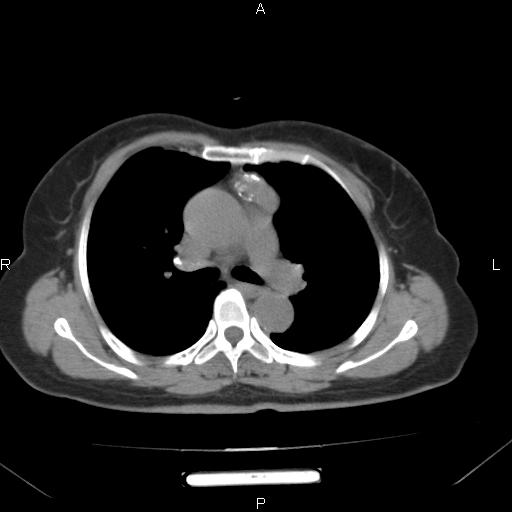

胸腺瘤

女、63Y 双眼睑下垂,早轻晚重。 胸腺瘤???

结果胸腺瘤